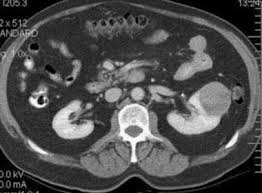

The cause of kidney cancer is unknown. Kidney cancer is the abnormal growth of cells in kidney tissue. The most common type is renal cell carcinoma (rcc), which accounts for more than 80% of all kidney cancers. Familial renal cancer people with this condition develop tumors called paragangliomas of the head and neck region and thyroid cancers. While the exact cause of a person's kidney cancer may not be known, certain risk factors are strongly linked to the disease, including smoking tobacco and obesity.

Doctors are still unable to pinpoint the exact cause of kidney cancer, however, they have picked up on a few common factors that may increase one's risk. A cancerous or malignant tumor can spread (metastasize) to other tissues and vital organs. Doctors know that kidney cancer begins when some kidney cells develop changes (mutations) in their dna. On that note, african americans develop kidney cancer more often than caucasians. Causes of kidney cancer the exact cause of kidney cancer is unknown, but some things can increase your chances of getting it, including: Being exposed to toxins in. Protect your kidneys throughout your kidney cancer journey It's not clear what causes most kidney cancers. Signs and symptoms of kidney cancer though renal and transitional cancer types affect the kidney in slightly different ways, the signs and. Smoking is not only bad for your lungs, but also can cause negative impact to other many parts of the body (including the kidneys). Bladder cancer most often begins in the cells (urothelial cells) that line the inside of your bladder. Paraneoplastic syndromes are clusters of symptoms that occur due to the production of hormones or other substances by tumor cells.with kidney cancer, these syndromes may lead to a high calcium level in the blood, with symptoms such as nausea and vomiting, weakness, and confusion, an elevated red blood cell count (erythrocytosis), and an increase in liver function tests even when a tumor hasn't. It has been over 60 years since hodges and huggins described a relationship between serum testosterone levels and prostate cancer progression. later in 1982, fowler and whitmore reported that exogenous testosterone given to patients with metastatic prostate cancer had worse outcomes. today androgen deprivation therapy remains a cornerstone of treatment for.

Kidney Cancer Diagnosis Portland Oregon City Cancer Treatment from ivcnorthwest.com When cancer starts in the kidney, it is called kidney and renal pelvis cancer. While women have androgens in their bodies, men have much higher levels, and this could. Paraneoplastic syndromes are clusters of symptoms that occur due to the production of hormones or other substances by tumor cells.with kidney cancer, these syndromes may lead to a high calcium level in the blood, with symptoms such as nausea and vomiting, weakness, and confusion, an elevated red blood cell count (erythrocytosis), and an increase in liver function tests even when a tumor hasn't. Familial renal cancer people with this condition develop tumors called paragangliomas of the head and neck region and thyroid cancers. The number one factor is age. Researchers found that men were five times as likely to suffer from kidney cancer that spread to the lungs. Kidney cancer is more prevalent in people over the age of 40 and continues to increase with each passing year. It is caused by defects in the genes sdhb and sdhd.